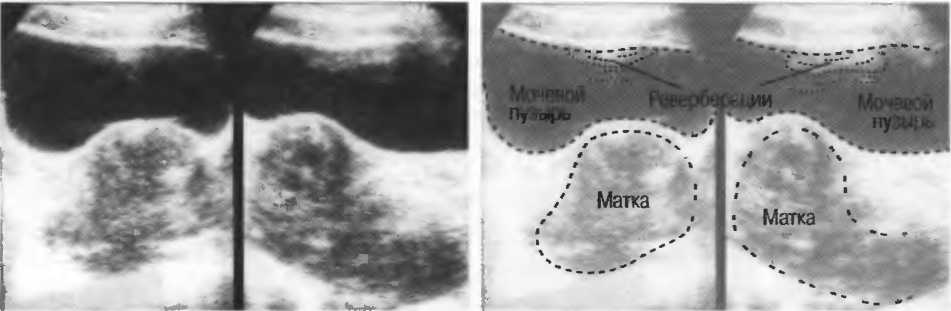

Реверберации могут полностью менять изображение, создавая линейные структуры или зеркальное отображение. Например, реверберации между параллельными слоями подкожных тканей создают параллельные линейные структуры в мочевом пузыре (рис. 20в).

Рис.20в. При сканировании матки через наполненный мочевой пузырь параллельные датчику слои тканей передней брюшной стенки могут вызывать появление ревербераций, которые определяются как зхоструктуры в передних отделах мочевого пузыря на фоне анэхогенной полости. Поперечный срез (слева) отличается от продольного среза (справа) при изменении положения датчика.